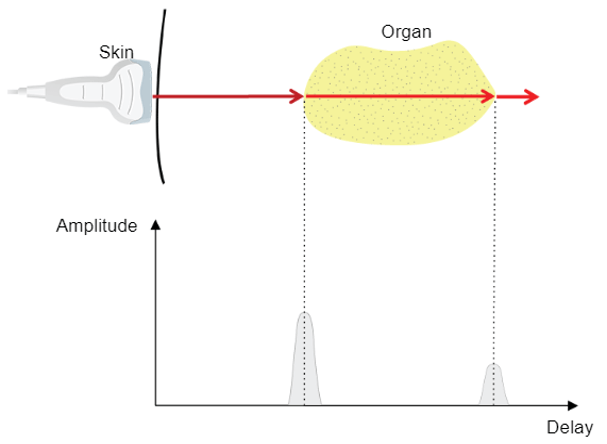

A-Mode

Different ultrasound modes are used in medical imaging today. The A-Mode, or Amplitude Modulation, was the first discovered mode. It is the display of amplitude spikes of different heights, where it consists of an X and Y axes. The X-axis represents the depth, while the Y-axis represents the Amplitude. This image shows an example of the A-Mode display.

The A-mode is mainly used for ophthalmology studies, to detect findings in the optic nerve. Delays are used to determine the depth of an organ, or otherwise to estimate the dimensions of an organ.